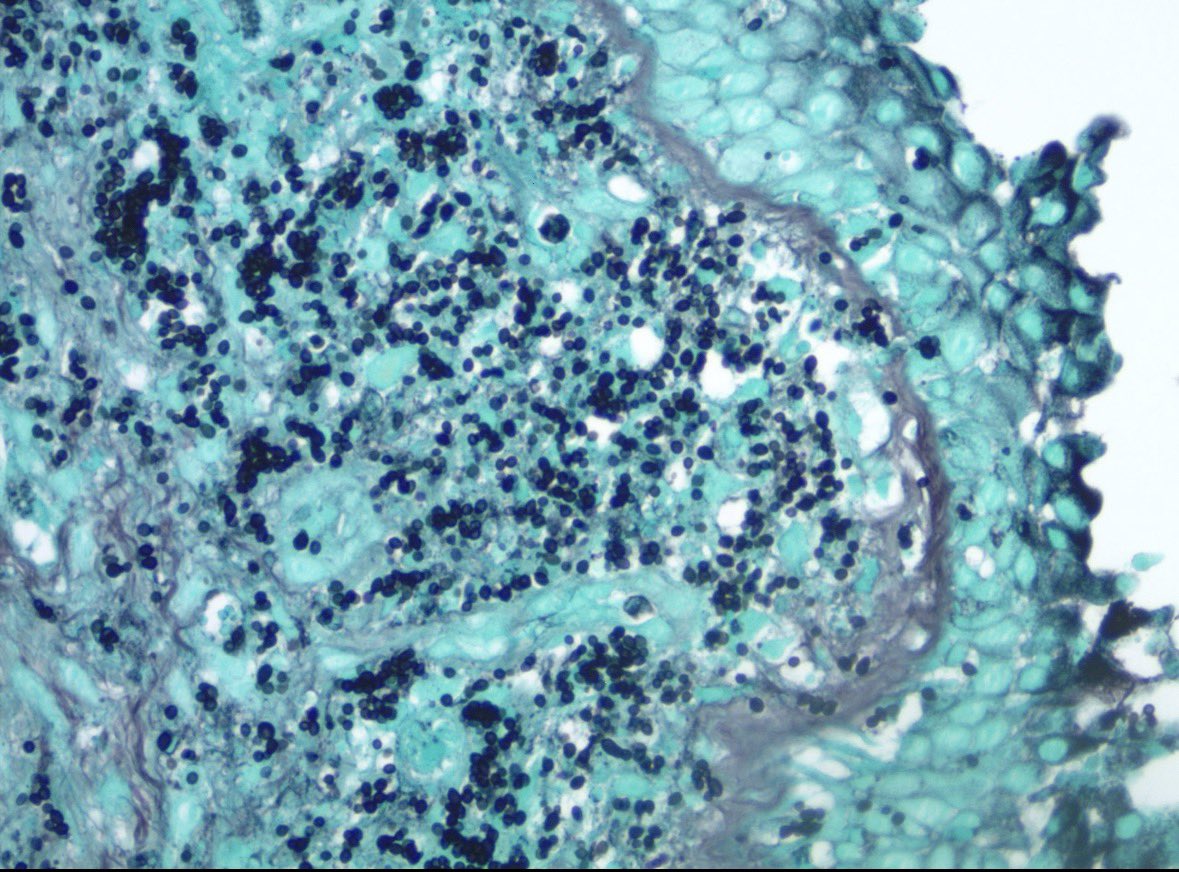

Incidental finding. Resection for met CA + CHF hx. Anything striking in alveolar septae imgs? Consider thoracic path training @MoffittNews "to contribute to the prevention and cure of cancer, focusing on groundbreaking research, expert patient care, and comprehensive education"